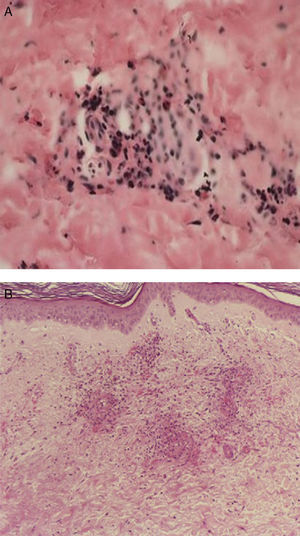

En el contexto de la ruta diagnóstica, el examen histológico es considerado el estándar de oro en las vasculitis. A pesar de ello, no siempre se obtiene el diagnóstico. Por ejemplo, en el caso de la biopsia de la arteria temporal, puede existir un 10% de pacientes en quienes no se hallan las características histopatológicas conocidas, incluso en centros de excelencia. La naturaleza segmentaria de la enfermedad explica en parte esto28. De igual forma, en un cierto subgrupo de pacientes con lesiones histológicas características en biopsias renales29 o cutáneas (figs. 2 y 3), los hallazgos pueden no correlacionar del todo con los resultados de los ANCA. En todo caso, las manifestaciones clínicas, apoyadas en lo posible por métodos de imagen que muestren afección de determinados órganos en forma más objetiva, pueden guiar la obtención de tejido con fines confirmatorios. Por ejemplo, la biopsia renal es particularmente útil en el diagnóstico de las VAA y la exclusión de otras enfermedades, como neoplasias o infecciones. Además, las características histológicas proporcionan oritentación pronóstica en la glomerulonefritis asociada a ANCA30. Por otra parte, la utilidad de la biopsia se extiende en algunos casos a demostrar la presencia de cicatrización con daño funcional. También, dada la ausencia de biomarcadores más específicos que correlacionen adecuadamente con el grado de actividad inflamatoria de la enfermedad, el examen histológico puede ser el único medio de exclusión de inflamación activa y puede guiar las decisiones terapéuticas. Si bien siempre será deseable obtener tejido histológico para la confirmación del padecimiento sospechado, algunas condiciones no siempre lo permiten. Por ejemplo, en un paciente con nódulos pulmonares, que se encuentre en ventilación mecánica, con diátesis hemorrágica e inestabilidad hemodinámica, la obtención de tejido adecuado para la confirmación histológica es difícil. En este contexto, la exclusión por todos los medios posibles de otras condiciones que expliquen la manifestación clínica que hizo sospechar una vasculitis y la indicación, realización correcta, así como la adecuada interpretación de las pruebas serológicas, como los ANCA, pueden ser clave para la toma de decisiones inmediatas, lo que permite esperar un mejor momento para obtener confirmación histológica, la cual es deseable en casos complejos.

A y B). La biopsia de la piel afectada mostrada en la imagen anterior presenta en el panel superior, infiltrado en la dermis papilar, con extensión a la dermis reticular (40×) y un acercamiento, en el panel inferior, del infiltrado que ocupa toda la pared del vaso sanguíneo, con leucocitoclasia (100×, HE).